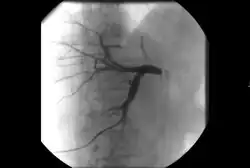

Angiography: Imaging the blood vessels to look for abnormalities with the use of various contrast media, including iodinated contrast, gadolinium based agents, and CO2 gas.[3]

Angiography: Sometimes referred to as traditional angiography, catheter angiography or digital subtraction angiography (DSA). A small needle is inserted into a blood vessel, then exchanged for a catheter over a wire. The catheter is directed at the vessel to be studied, and contrast is directly injected to evaluate the lumen under video X-ray. This is an older technique than modern CT angiography or MR angiography, but provides unique advantages. With a catheter in place, provocative maneuvers can be performed such as breath holds or instillation of vasodilators, to evaluate a patient's blood flow dynamically. This can reproduce symptoms and identify functional abnormalities in a vessel that a static CT or MR imaging cannot.[80][81] Angiography provides the basis for all endovascular therapy.